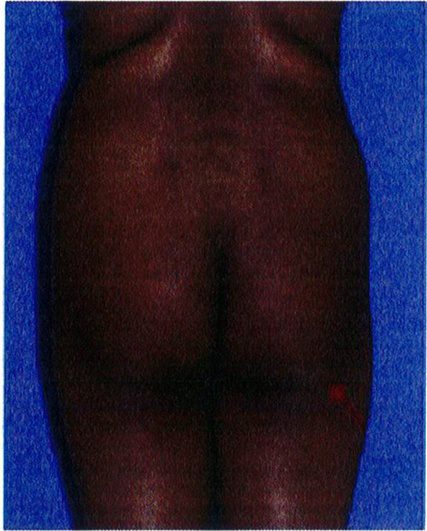

Bước cuối cùng khi đánh giá vùng mông là đánh giá tình trạng sa mông. Đế đánh giá, nên đứng ỏ phía bên để nhìn và phân loại sa mông (từ không sa đến có sa), cả 2 loại này đều được phân loại thành 3 phân lớp phía dưới chúng. Việc phân loại này quyết định xem nên thực hiện quy trình nào cho bệnh nhân.

Ở những bệnh nhân không có sa mông, toàn bộ vùng mông nằm trên nếp lắn mông và không có phần da thừa nằm dưới nếp lằn.

Tuy nhiên, dựa trên hình dạng vùng mông của đa số những bệnh nhân này, có thể chia thành 3 lớp: A, B và C (Hình 27).

ở những bệnh nhân thuộc lớp này, hầu hết phần mông nằm ở tập trung ở giữa, mô mỡ dưới da được phân bố đều ở phần mông trên và mông dưới. Ở mặt bên, không phát hiện tình trạng sa hoặc các vết lõm trên bề mặt, bờ mông có hình chữ C mềm mại. Lớp A này là hình dáng lý tưởng cho vùng mông, đặc biệt có tính thẩm mỹ cao khi nhìn từ phía bên. Những bệnh nhân thuộc lớp này chỉ cần thực hiện thủ thuật nâng mông đơn thuần.

Trong lớp C, da không bị xệ xuống dưới nếp lằn mông nhưng nếp này cũng không được nhìn thấy rõ ràng. Mỡ phân bố đều khắp mông khi nhìn từ phía bên. Phẫu thuật làm đầy mông nên được chỉ định cho những bệnh nhân này.

Lớp B

Về cơ bản, các bệnh nhân ở lớp B có hình dáng mông điển hình như sau: không có phần da chùng xuống phía dưới nếp lắn mông, nhưng có sự xuất hiện các vết lõm ở nửa dưới của phần trung tâm, dẫn tới bờ mông không có đường cong mềm mại (Hình 27). Đối với bệnh nhân thuộc lớp này, nên phối hợp thực hiện Nâng mông với cấy mỡ tự thân. Implant cũng giúp ích trong một số trường hợp. Việc chuyển mô mỡ từ vùng này qua vùng khác có thể được thực hiện ngay tại thời điểm phẫu thuật hoặc được coi như giai đoạn 2 của phẫu

Class A – No ptosis

Class B – No ptosis: depression, lower part of central zone

Class C – No ptosis at crease

Hình. 27. Phân loại các bệnh nhân không có sa mông theo 3 lớp A, B, và C. Đường nét đứt biểu thị cho nếp lắn mông nhìn từ phía bên (đôi khi được gọi là crease).

Class A- No ptosis: Lớp A – Không sa Class B – No ptosis: depression, lower part of central zone: Lớp B – Không sa: Lõm ở phía dưới vùng trung tâm.

Class A- No ptosis: Lớp A – Không sa Class B – No ptosis: depression, lower part of central zone: Lớp B – Không sa: Lõm ở phía dưới vùng trung tâm. Class C – No ptosis at crease: Lớp C – Không sa xuống dưới nếp lằn mông. Gluteal crease line : Nếp lắn mông

Class C – No ptosis at crease: Lớp C – Không sa xuống dưới nếp lằn mông. Gluteal crease line : Nếp lắn mông